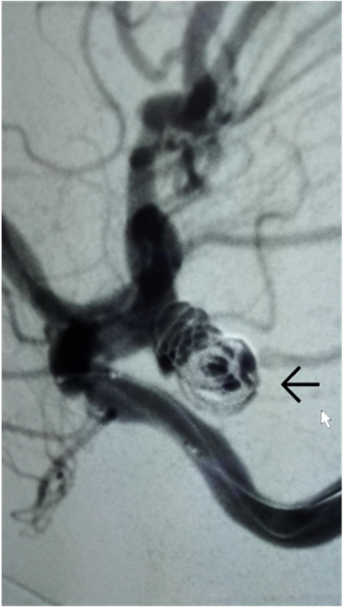

女性,63岁,蛛网膜下腔出血,后交通动脉瘤破裂出血,动脉瘤大,易再出血,死亡率达60%以上。行血管内动脉瘤栓塞术,手术安全、创伤小、效果好,避免再出血风险。

手术后,动脉瘤被栓塞(箭头处)